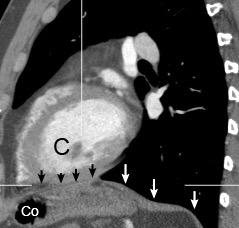

Aneurisma aórtico intracrural

/Restrepo CS et al. The diaphragmatic crura and retrocrural space: normal imaging appearance, variants, and pathologic conditions. Radiographics 2008